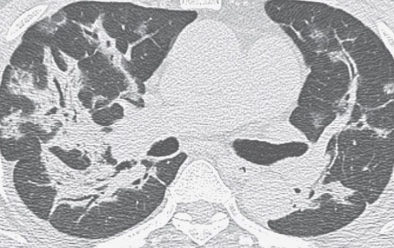

- Consolidations en patch, Verre dépoli

- Distribution sous-pleurale et péribronchovasculaire

- Bilatérales ++, Asymétriques

- Reverse Halo sign (Atoll sign = 20% des cas mais spécifique)

- Bandes de Condensations Hilo-périphériques contenant des bronchogrames aériques (spécifique)

Consolidations et VD sous-pleural et péribronchovasculaire

Reverse Halo Sign, Bandes de condensations hilo-périphériques avec bronchogramme aérique